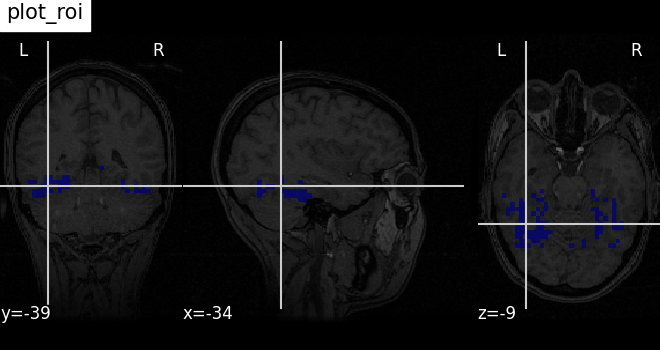

Plotting ROIs (here the mask) with function plot_roi¶

Visualizing ventral temporal region image from haxby dataset overlaid on subject specific anatomical image with coordinates positioned automatically on region of interest (roi)

plotting.plot_roi(

haxby_mask_filename, bg_img=haxby_anat_filename, title="plot_roi"

)

<nilearn.plotting.displays._slicers.OrthoSlicer object at 0x7f3bd0d2f530>